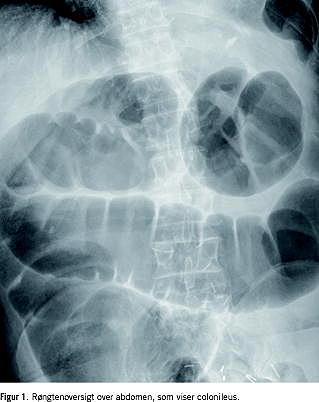

Oversigt over abdomen viste colonileus med flere væskespejl (Figur 1 ). Colonindhældning viste en ca. 2 cm lang tumorlignende striktur med trådtynd kontrastpassage, som svarede til den proksimale colon decsendens (Figur 2 ).